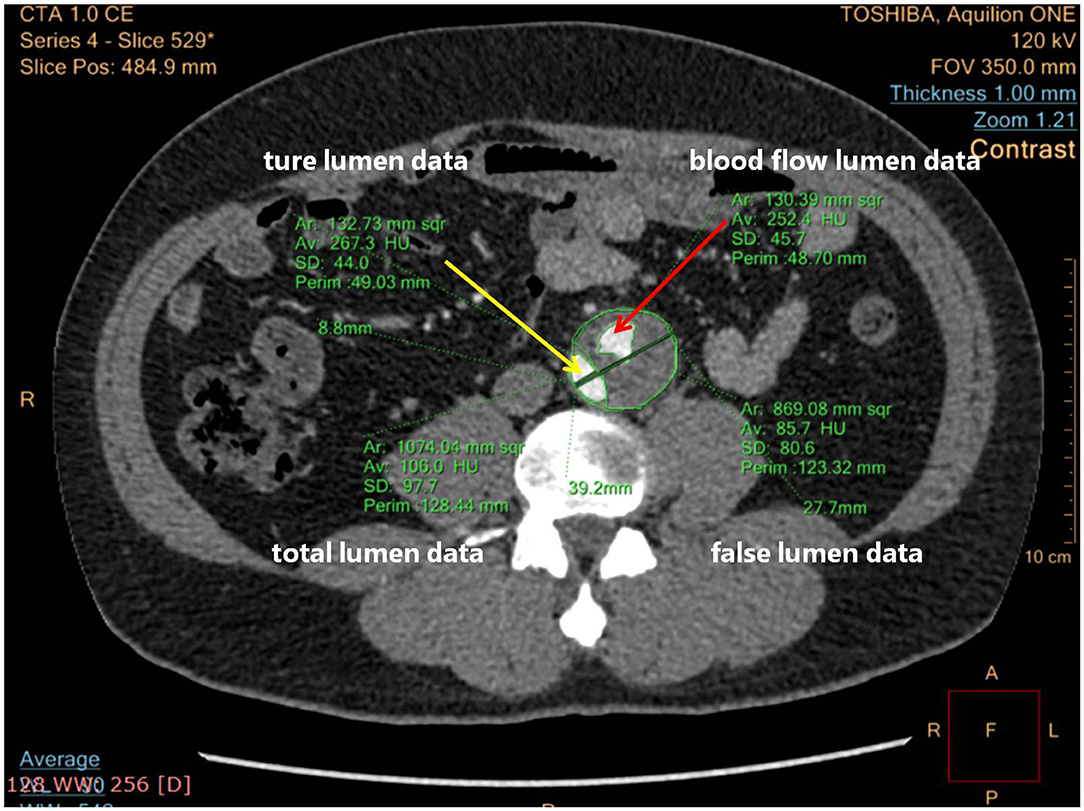

The maximum intensity projection (MIP) mode of CTA was used to show how endovascular devices were used, and three-dimensional reconstructions were used for remodeling of the aorta (22). The FLT status was assessed in two ways: blood flow area in FL, or ratio between it and FL area, especially at the level of the maximum aortic dilatation. Figure 3 shows how the total aortic lumen, true lumen, FL, and blood flow lumen were measured. Blood flow lumen means the cavity of flowing blood the in FL. The blood flow areas mentioned above were measured by software analysis to outline the contour of the blood flow, reading the area, and summing them.

Figure 3. Computed tomographic angiography (CTA) cross-section measuring details blood flow lumen. The yellow arrow points to the true lumen; the red arrow points to the blood flow lumen.